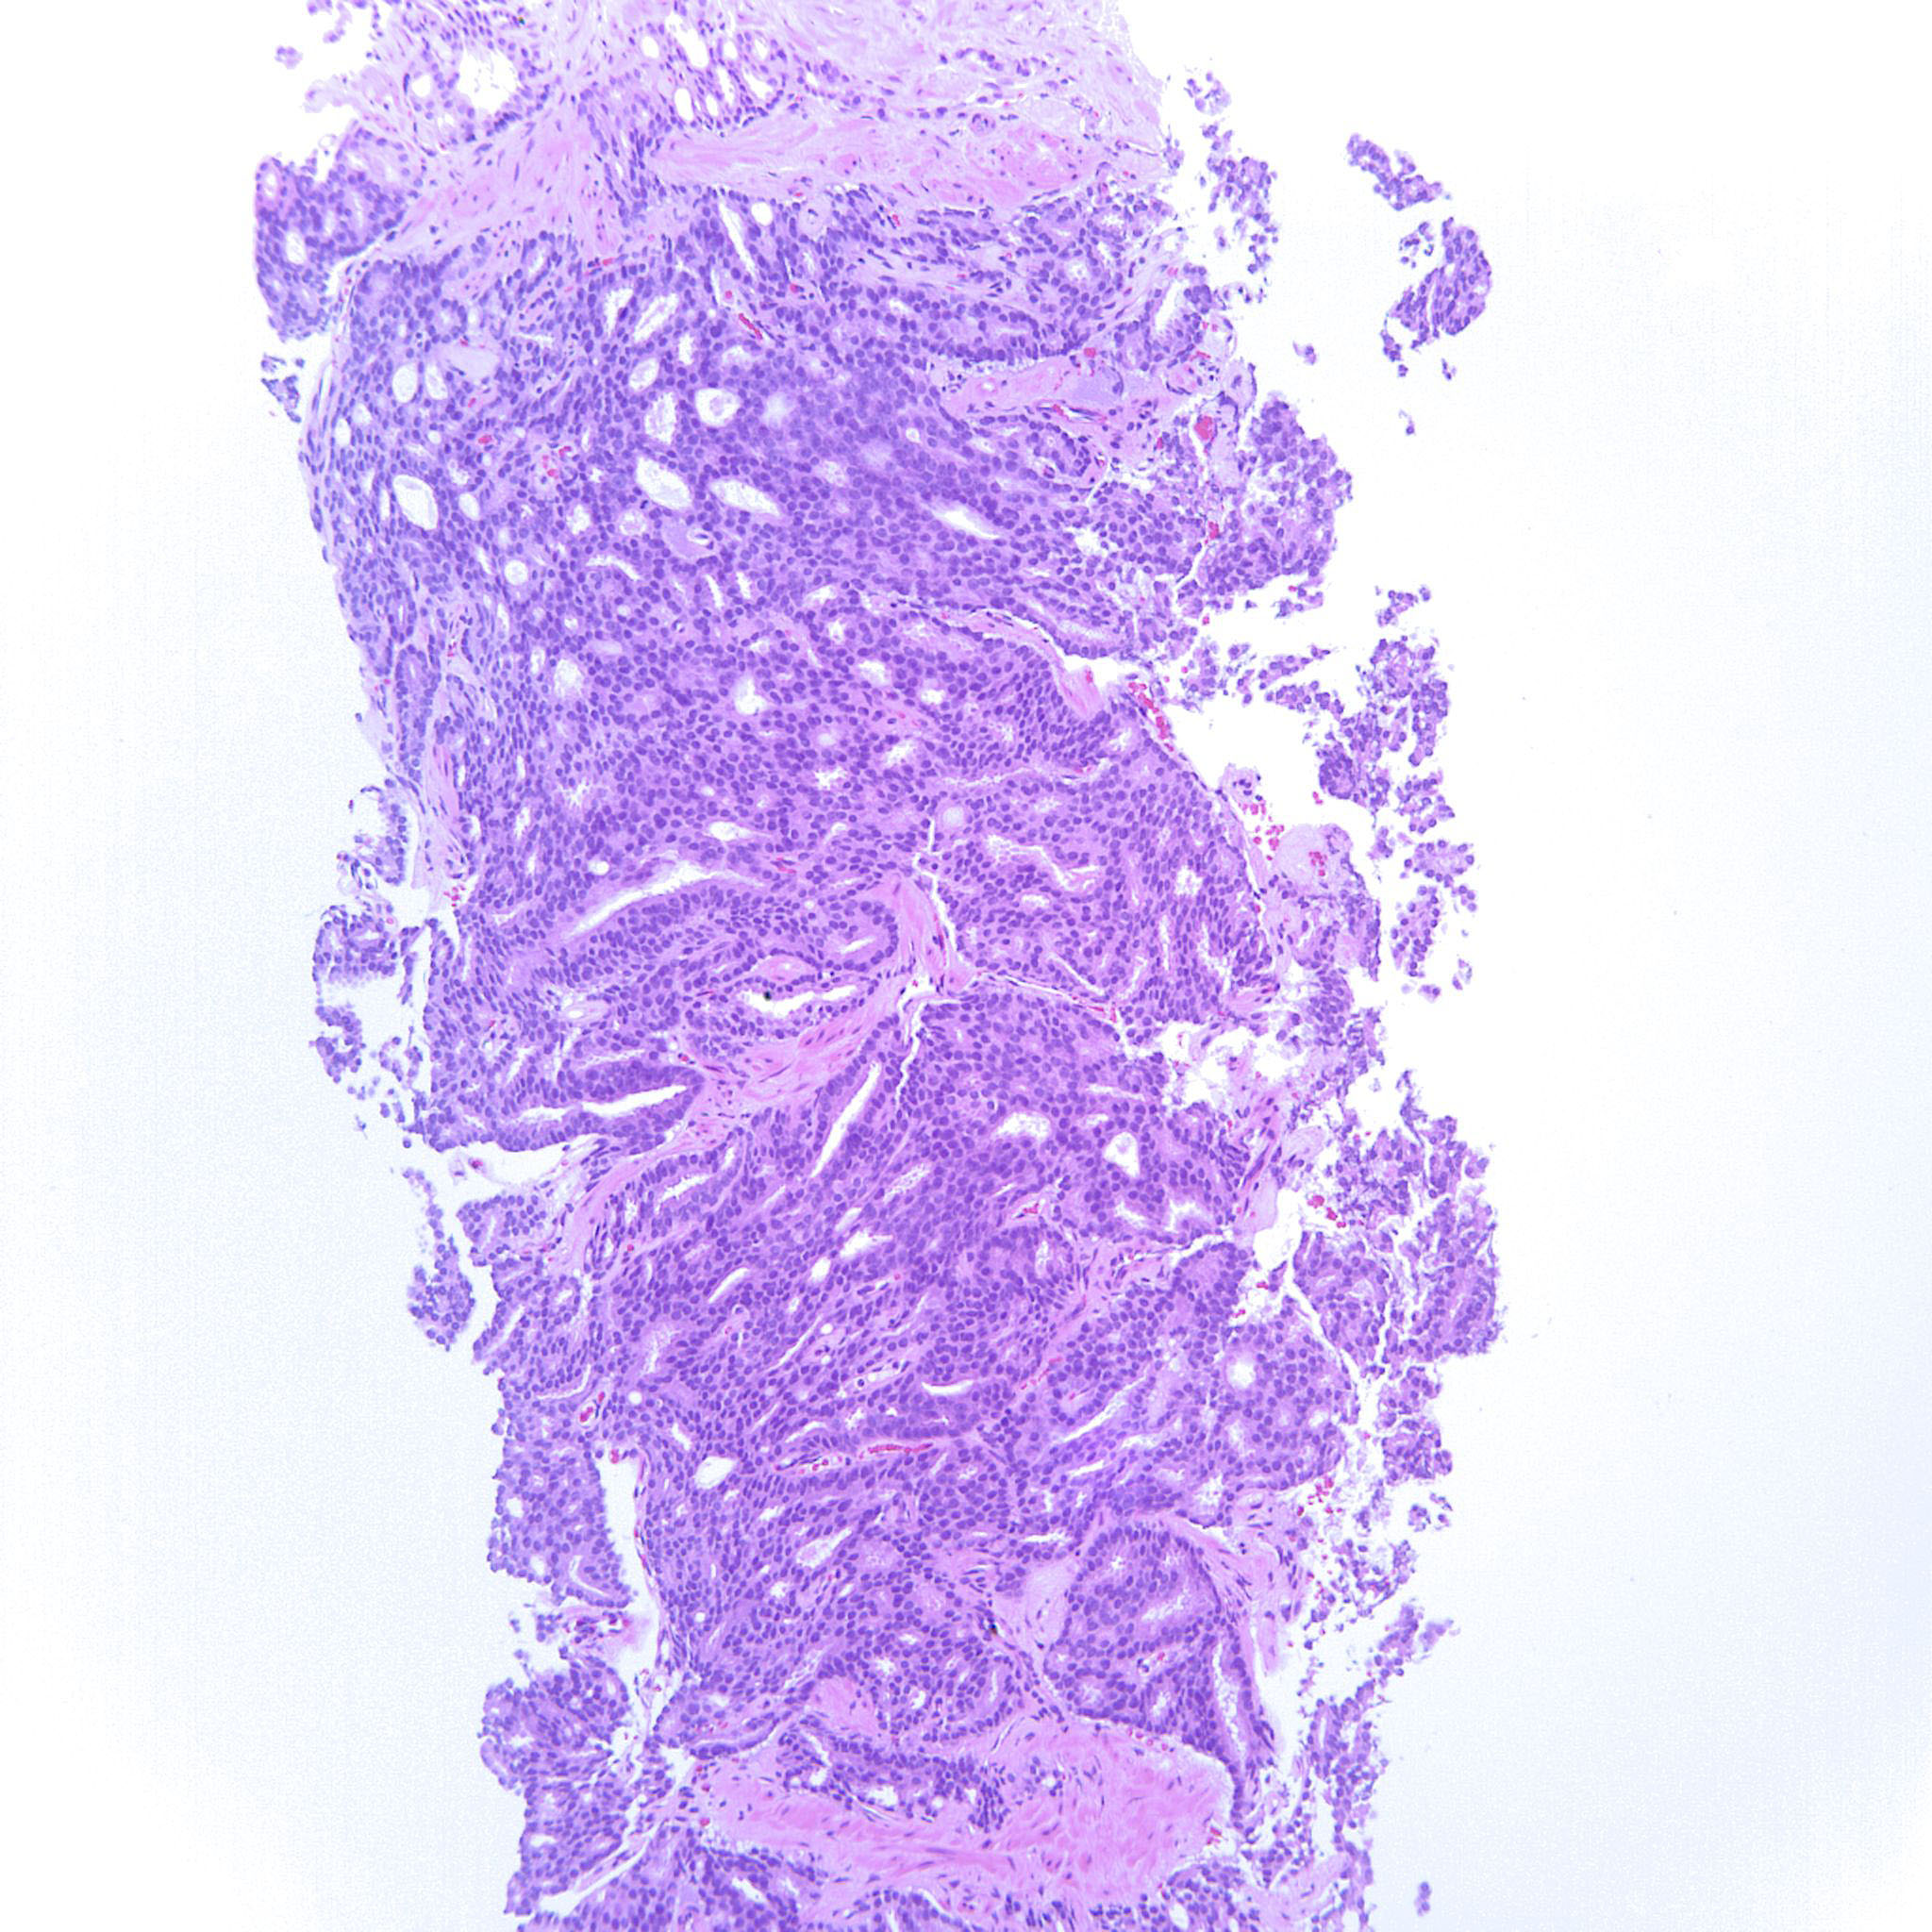

Prostate cancer grading

Case ID: 227